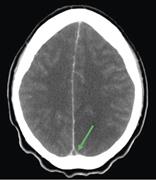

Penetration of a divided cystoperitoneal shunt catheter into the transverse colon inducing acute mastitis

Kentaro Shimodaira and others

Journal of Surgical Case Reports, Volume 2013, Issue 5, May 2013, rjt039, https://doi.org/10.1093/jscr/rjt039